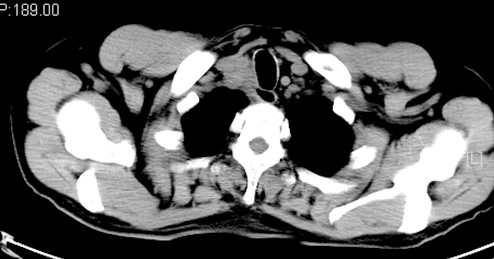

X-Ray:上纵隔增宽,气管略偏移。颅骨、双侧肩胛骨、锁骨、肋骨和骨盆平片未见骨损害。 颈部及胸部CT:右锁骨上及前纵隔肿大淋巴结影,压迫气管,最大径约6.5cm,部分血管受侵可能。后纵隔食管周围见肿大淋巴结影压迫食管,右侧少量胸腔积液,食管中段局部管壁增厚。腹部CT:腹膜后多枚小淋巴结(最大径1cm),,胆囊炎,胆囊结石,脾肿大,前列腺钙化灶。

化疗前:

化疗后